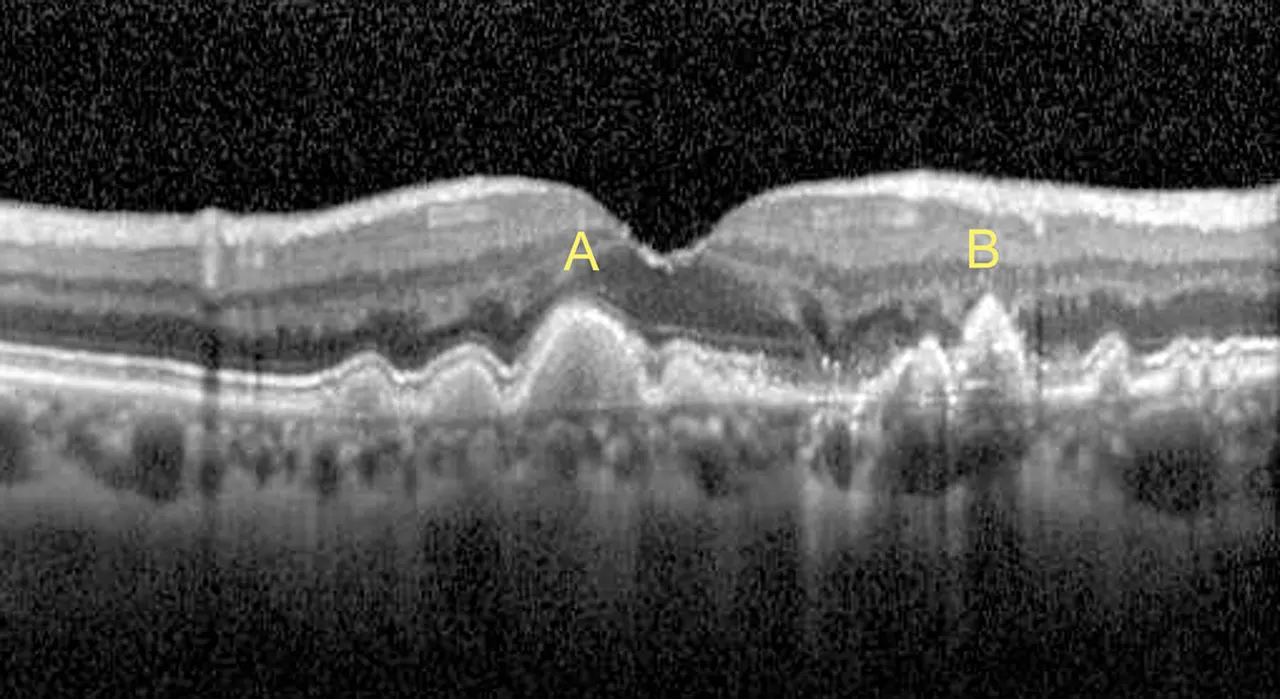

Η Ξηρή Μορφή (dry AMD) της ΗΕΩΚ είναι η πιο συνηθισμένη μορφή, αντιπροσωπεύοντας περίπου το 85-90% των περιπτώσεων. Χαρακτηρίζεται από τη βαθμιαία φθορά των φωτοϋποδοχέων και του μελάγχρου επιθηλίου της ωχράς κηλίδας. Οι ασθενείς βιώνουν σταδιακή μείωση της όρασης, με συχνότερα συμπτώματα τη θόλωση και την αίσθηση σκοτεινών κηλίδων στο οπτικό τους πεδίο.